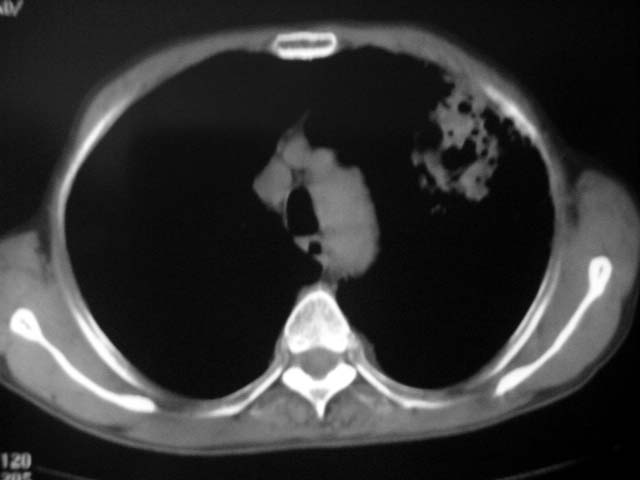

以下是引用zjzjr在2007-9-4 17:00:00的发言:[br]双上肺继发型结核伴左上肺空洞形成.慢性支气管炎伴肺气肿.

以下是引用liuzheng_9326在2007-9-4 16:23:00的发言:[br]痰检未见结核菌, 治疗后症状好转。图像符合陈旧性结核伴感染。